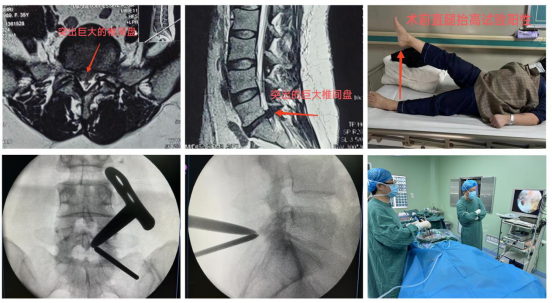

骨科近期收治了一位35岁女性患者,主诉“右下肢抽痛、麻木半年,加重2月”,行走约50米后,右下肢疼痛难忍,严重影响生活质量。靳占奎副主任医师对患者进行了一系列检查和严格的鉴别诊断,认定该患者“腰椎间盘突出症”诊断明确,且患者经过半年以上的保守治疗无显著疗效,具有明确手术指征。靳占奎副主任医师指导县21点策略

充分完善UBE技术必备的硬件条件,为患者顺利实施了“微创单侧双通道脊柱内镜下腰椎间盘髓核摘除术”。术后患者右下肢疼痛缓解,患者非常满意。

微创单侧双通道脊柱内镜(UBE)技术是治疗腰椎间盘突出症的经典微创手术方式,相较于其它微创手术,该技术入路更接近开放手术,学习曲线相对平缓,镜下视野更全面,操作通道可以应用类似开放手术的器械,安全性高。该手术目前是21点技巧中心

骨科脊柱微创手术治疗的一大特色。